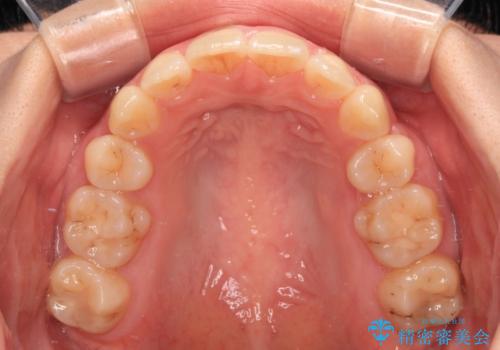

口の閉じにくさが改善され、横顔のシルエットも大幅に改善されました。